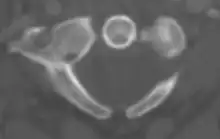

The atlas's chief peculiarity is that it has no body,[3] which has fused with the next vertebra.[4] It is ring-like and consists of an anterior and a posterior arch and two lateral masses.

Anterior arch

The anterior arch forms about one-fifth of the ring: its anterior surface is convex, and presents at its center the anterior tubercle for the attachment of the Longus colli muscles and the anterior longitudinal ligament; posteriorly it is concave, and marked by a smooth, oval or circular facet (fovea dentis), for articulation with the odontoid process (dens) of the axis.

Posterior arch

The posterior arch forms about two-fifths of the circumference of the ring: it ends behind in the posterior tubercle, which is the rudiment of a spinous process and gives origin to the Recti capitis posteriores minores and the ligamentum nuchae. The diminutive size of this process prevents any interference with the movements between the atlas and the skull.

Lateral masses

The lateral masses are the most bulky and solid parts of the atlas, in order to support the weight of the head.

Each carries two articular facets, a superior and an inferior.

- The superior facets are of large size, oval, concave, and approach each other in front, but diverge behind: they are directed upward, medially, and a little backward, each forming a cup for the corresponding condyle of the occipital bone, and are admirably adapted to the nodding movements of the head. Not infrequently they are partially subdivided by indentations which encroach upon their margins.

- The inferior articular facets are circular in form, flattened or slightly convex and directed downward and medially, articulating with the axis, and permitting the rotatory movements of the head.

Vertebral foramen

Just below the medial margin of each superior facet is a small tubercle, for the attachment of the transverse atlantal ligament which stretches across the ring of the atlas and divides the vertebral foramen into two unequal parts:

- the anterior or smaller receiving the odontoid process of the axis

- the posterior transmitting the spinal cord (medulla spinalis) and its membranes

This part of the vertebral canal is of considerable size, much greater than is required for the accommodation of the spinal cord.

Transverse processes

The transverse processes are large; they project laterally and downward from the lateral masses, and serve for the attachment of muscles which assist in rotating the head. They are long, and their anterior and posterior tubercles are fused into one mass; the foramen transversarium is directed from below, upward and backward.